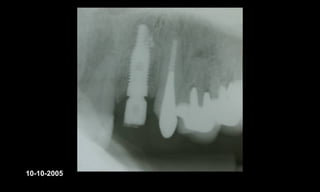

10-10-2005

Novembro de 2005

24-01-2006